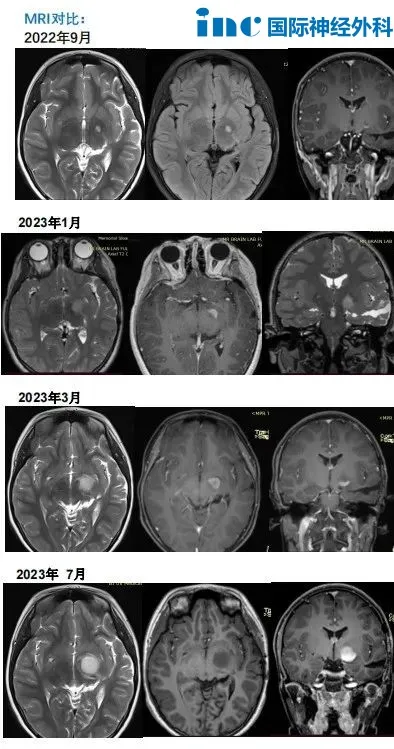

2022年复查MRI显示左侧丘脑出现异常信号,2023年复查发现病灶明显增大。经靶向药物治疗三个月后,MRI显示病灶进一步增大并强化,肿瘤尺寸从1.7cm×1.6cm进展至1.8cm。